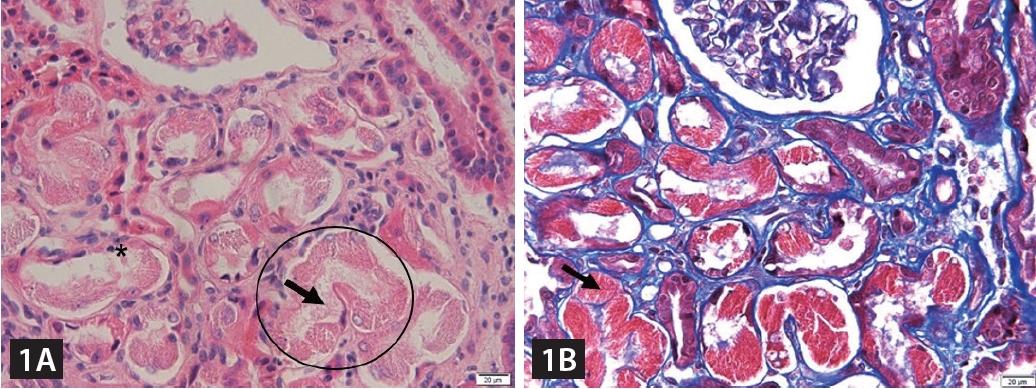

Additional blood and urine tests and kidney biopsy were performed to determine the potential causes of renal insufficiency with FS. Urine protein electrophoresis revealed an M-spike in the beta-globulin region, whereas serum immunoglobulin electrophoresis revealed an abnormal sedimentation line in the kappa region. The free kappa/lambda ratio was elevated to 1,133.86. The kidney biopsy showed abundant granular/elongated, and weakly eosinophilic crystals in the proximal tubular cell cytoplasm and the tubular lumen (Fig. 1). Ultrastructural examination clearly demonstrated electron-dense crystals with various shapes, ranging from rhomboid to pentagonal and elongated (Fig. 2). The bone marrow biopsy included 18% plasma cells, leading to the definitive diagnosis of multiple myeloma, light chain disease, kappa type.

FS is commonly caused by genetic disorders, exposure to heavy metals, or medications, but it can rarely present as a latent manifestation of light chain disease. The crystalline inclusions produced by light chains can lead to cytotoxicity in proximal tubular epithelial cells, resulting in proximal tubulopathy, whereas crystal-laden phagocytes can lead to tubular atrophy and interstitial fibrosis through tissue injury, as shown here. In patients with proximal tubulopathy accompanied by renal insufficiency and proteinuria, multiple myeloma, particularly light chain disease, should be considered in the differential diagnosis.